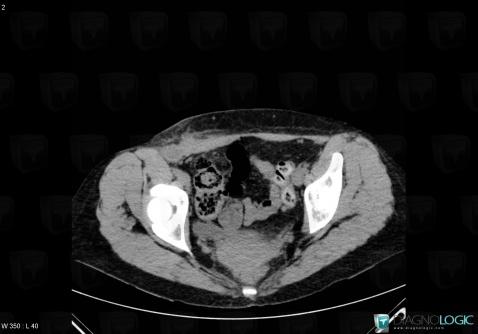

- Diagnosis Abscess, Location(s) Abdominal wall, with gamuts Abdominal wall mass